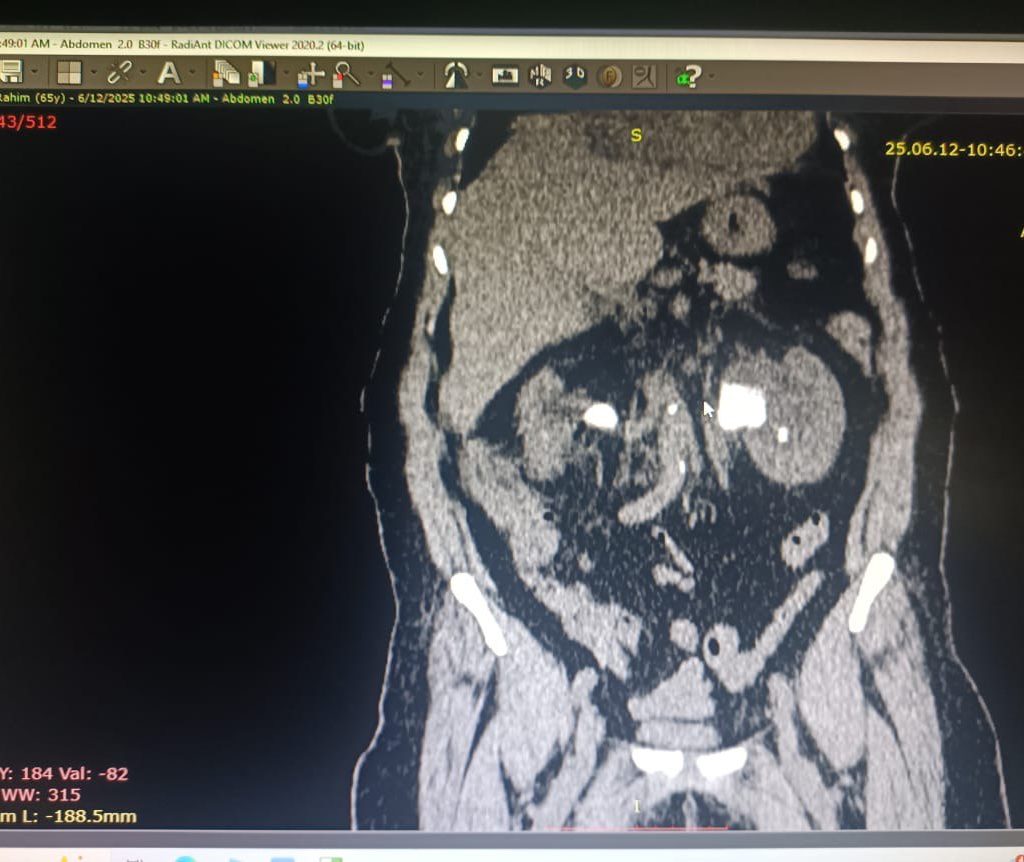

“بعد استقرار حالتها، وضعنا خطة علاجية متكاملة تضمنت إجراء عمليات ناظورية متتابعة. قمنا أولًا برفع حصى الكلية اليسرى بتقنية استخراج الحصوات عبر الجلد (PNL) من خلال فتحة صغيرة لا تتجاوز 1 سم، وهي تقنية دقيقة تسرّع التعافي وتقلل المضاعفات.”

“بعد شهرين أجرينا عملية رفع حصى الكلية اليمنى باستخدام تقنية ناظور الحالب والكلية المرن الحديثة، والتي مكنتنا من إزالة الحصوات بكفاءة عالية دون جراحة تقليدية.”